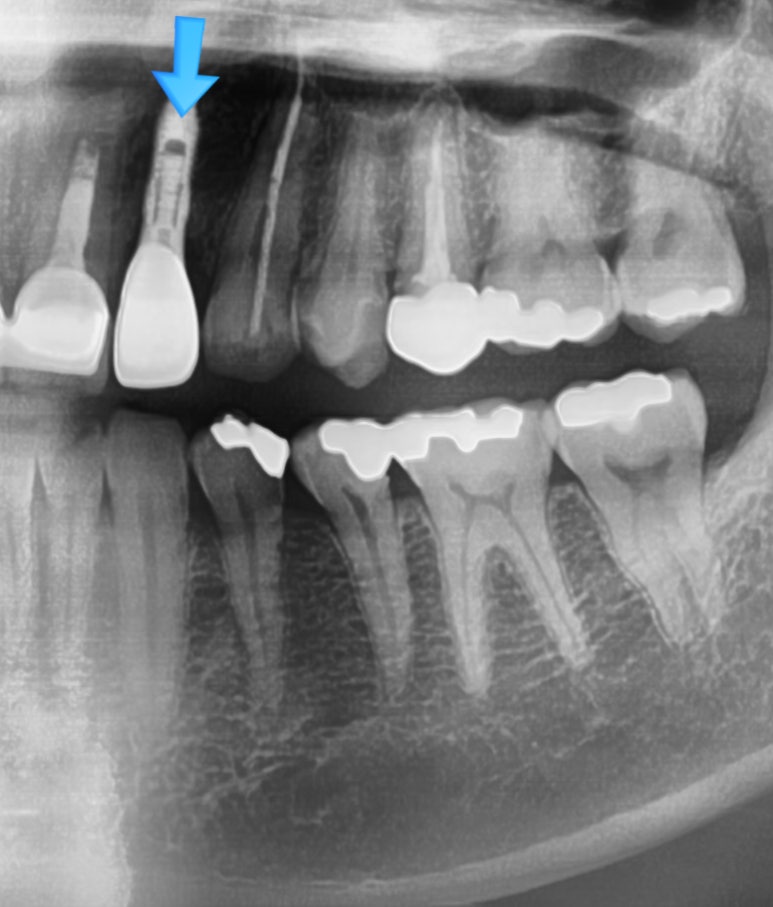

기존에 다른 치과에서 치료받은 치아가 부러진 상태로 오심 (부러진 머리를 끼워서 오셨으나 제거하고 찍은 상태)

![[시청역/서울역 치과] 앞니 치아부러짐 자연스럽게 치료사례 관련 이미지 12](https://pub-9f2bb3498faf4d1d8714b41df24753e3.r2.dev/content/clinics/archive/rseeanjxfu/naver_blog/yonseiyegam/assets/by_hash/59264360e5eb5ea384404f9d64aec71143b92431718f494db0c955179809b65d.jpg)

네비게이션 임플란트를 통해 정확한 각도로 식립하고자 함

임플란트 전 후 사진

이 분 같은 경우는 남은 뿌리를 빼면서 동시에 발치즉시 임플란트를 하셨습니다.